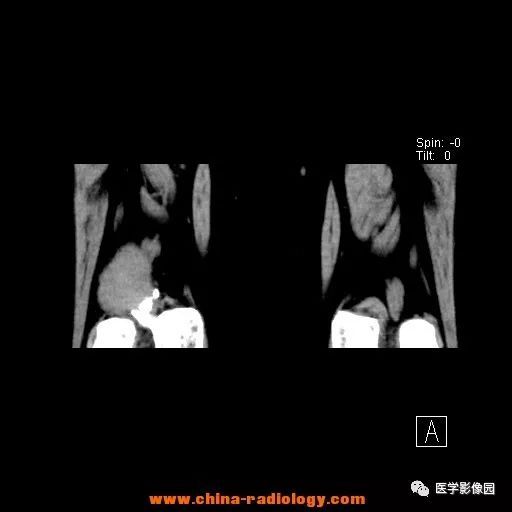

患者女性,29岁,右膝关节痛疼3月余,局部无红肿。

影像学表现:右股骨远端外后方可见局限性骨质破坏及软组织肿块,边界清楚。

病理结果:梭形细胞瘤